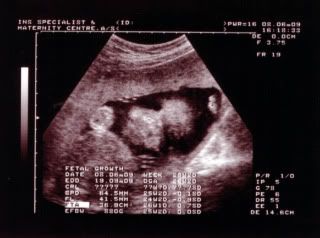

有那么明显吗?? 还看到宝宝的嘴巴像爸爸。。  |